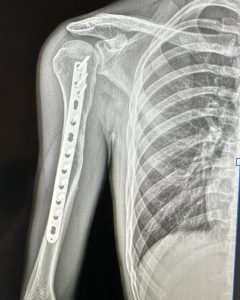

Клінічний випадок. Пацієнт звернувся до нас зі скаргами на утворення у верхній третині плеча, яке заважало притиснути руку до тулуба, а також на оніміння пальців кисті. Після клінічного огляду та рентгенологічного обстеження утворення було розцінене як остеохондрома.

Було виконано крайову резекцію плечової кістки з подальшим накістковим металоостеосинтезом, що дозволило усунути проблему та зберегти функцію кінцівки.